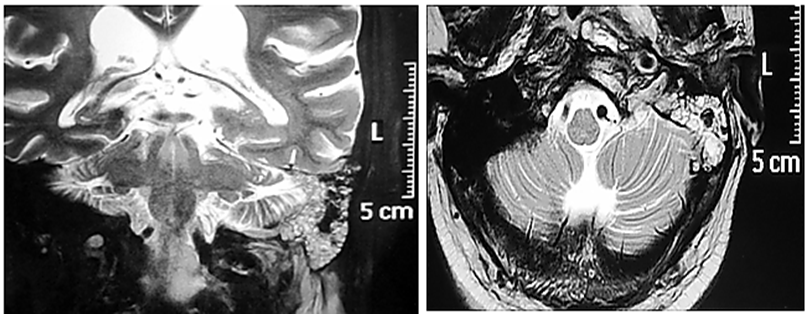

Thorough clinical examination revealed right hemiparesis, left Lateral rectus palsy suggestive of sixth cranial nerve palsy and deviation of angle of the mouth due to left Facial nerve Palsy (Lower Motor Neuron type) (Figure1). There was a palpable firm mass in the upper neck behind the angle of jaw on left side, post auricular lymphadenopathy and a positive Griesinger’s sign (Figure 2). Otoscopy revealed active mucopurulent discharge with granulations and necrotic tissue in external auditory canal and the middle ear (Figure 3). Magnetic resonance imaging and Contrast enhanced computed tomography temporal bones and neck revealed left coalescent mastoiditis with extension across the subperiostium with fluid collection involving the soft tissue of left postauricular region, extradural abscess from left petrous, basal meningitis and pontine infarct. Magnetic resonance venogram and angiogram revealed Central venous sinus thrombosis (CVST) of left sigmoid sinus, transverse and superior sagittal sinus, loss of luminal signal of left internal jugular vein at jugular bulb and decreased flow related to enhancement involving the petrous segment of the left internal carotid artery (ICA) (Figure 4).

Figure 4 MRI revealing the lesion extending from the mastoid into the brain up to the cerebellopontine angle and upper neck on left side.